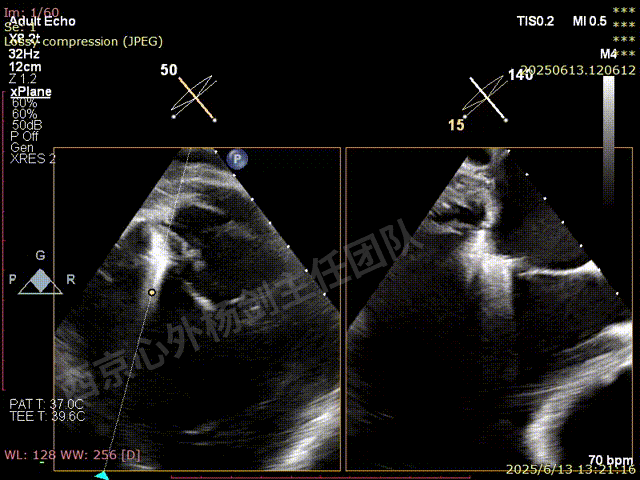

术前超声检查

图片

TAVR术后,全心增大,二尖瓣反流重度,三尖瓣反流重度。中量心包积液。左室严重增大,标准图像调整困难。主动脉瓣位带支架人工瓣膜瓣叶启闭正常,主动脉瓣位人工瓣上血流速度Vmax 148cm/s,PGmax 9mmHg,Vmean 86cm/s,PGmean 2mmHg, VTI 34.7cm,瓣周反流(轻)。估测肺动脉收缩压约49mmHg;左室收缩功能明显减低。LVEF:23%,EDV:364ml,ESV:221ml。

彩色血流示:二尖瓣反流缩流颈彩宽6.6mm,面积17cm²,容积30ml;二尖瓣瓣口面积6.6cm²,瓣环内径:左右径34mm,前后径34mm。2区瓣叶长度:前叶36mm,后叶20mm,叶环比1.6. 三尖反流面积17.2cm²,容积33ml,Vmax 291cm/s,PGmax 34mmHg。